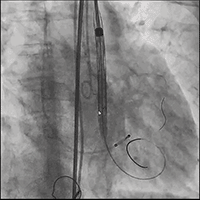

● 更换新瓣膜跨瓣后,猪尾难以送至无冠窦底,故行造影定位窦底。

隐约可见“无冠窦”后部更深窦底,位于“无冠窦”下约6mm,参考该位置后进行0位定位,无起搏逐步释放至工作位,瓣膜无明显位移表现,瓣膜形态压缩良好,造影评估无反流。准备释放瓣膜。

无张力释放,脱钩后瓣膜略微下滑,约位移瓣环下4~5mm位置,瓣膜整体形态良好,造影评估无可见反流。

超声评估,微量瓣周反流,二尖瓣工作良好,植入位置理想。

结束手术,一波三折终成功!